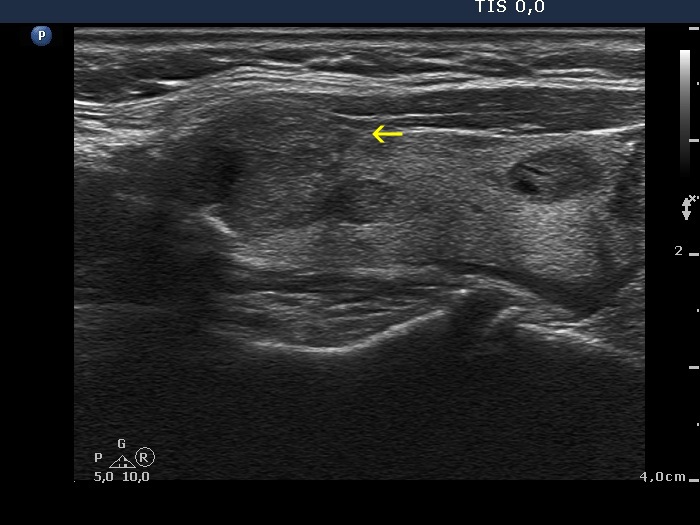

The borders of the nodule - case 1527 (ultrasonographic picture 4b)

Right lobe, longitudinal scan

Right lobe, longitudinal scan. The yellow arrow points to a spiculation.